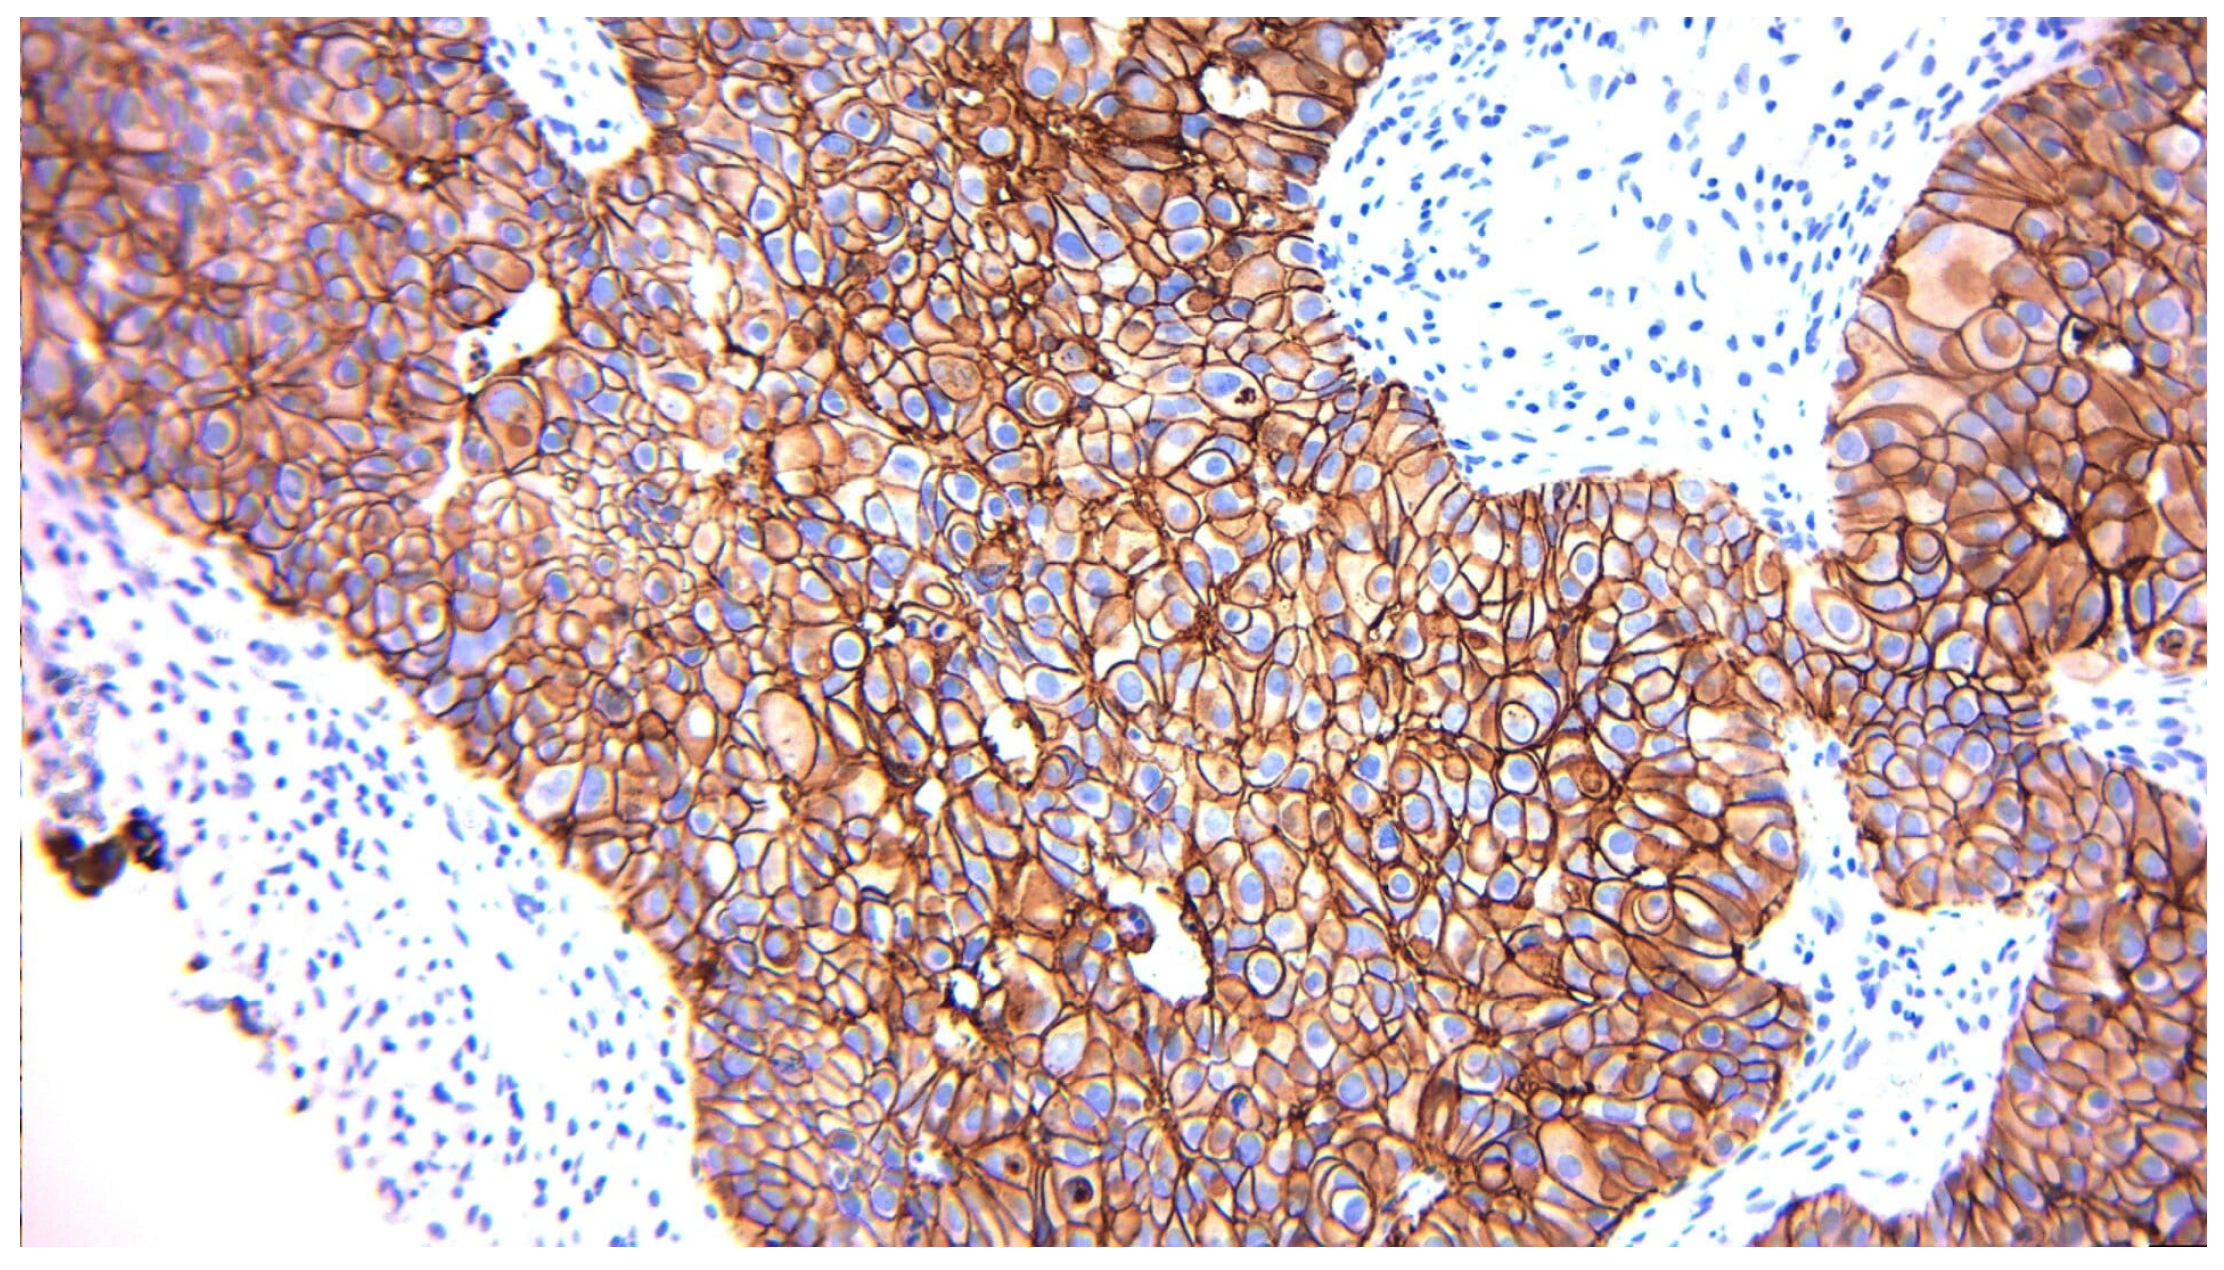

2.3. Biomarker Assessment

3.2.3. Correlation Between Pre-Surgery and Post-Surgery HER2